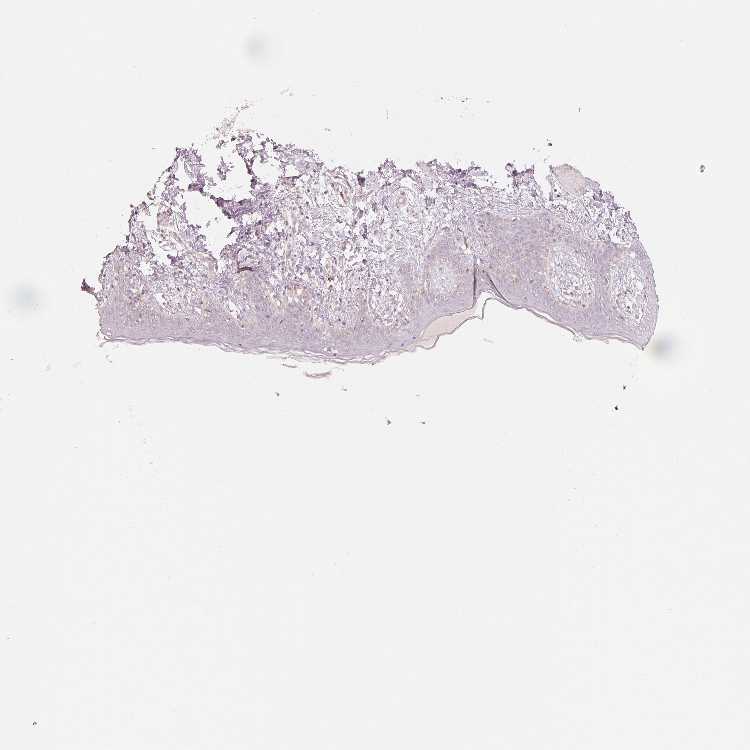

OR13C3